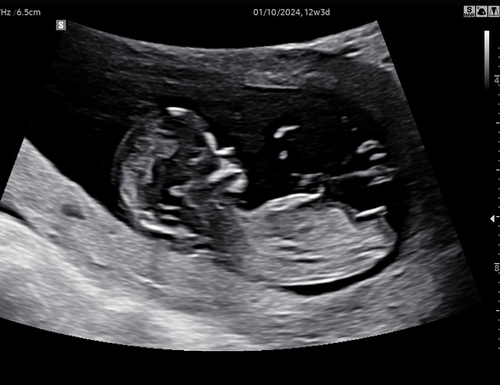

Wat denken jullie 🩷 of 🩵? 13 weken en 2 dagen

12 weken.. Is het al te zien en zo ja wat denken jullie? Ben zoooo benieuwd!!🩵🩷

Nog net geen 12 weken, 11+6. Toch iets te nieuwsgierig of jullie al een gokje kunnen wagen.